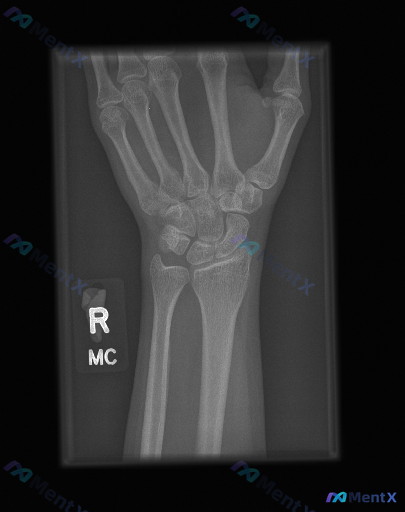

影像资料:右侧手腕正位X光片

- 骨骼完整性:远端桡骨、尺骨及所有腕骨(舟骨、月骨、三角骨、豌豆骨、大多角骨、小多角骨、头状骨、钩骨)皮质连续,无骨折线、台阶感或骨小梁破坏;

- 关节对位:桡腕关节、腕中关节及桡尺远侧关节(DRUJ)对位良好,Gilula三条腕骨弧线连续平滑,无脱位或半脱位;

- 骨密度与软组织:未见明显软组织肿胀影、脂肪垫移位或骨质密度异常改变;

- 综合结论:在当前投照角度下,未见明确的骨折或关节脱位征象,各腕骨排列关系大致正常,未见明显的退行性改变或骨质破坏。